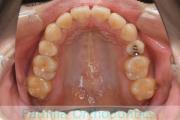

- ≫治療前

-

上顎

下顎

前歯の関係など

右側

正面

左側

- ≫治療後